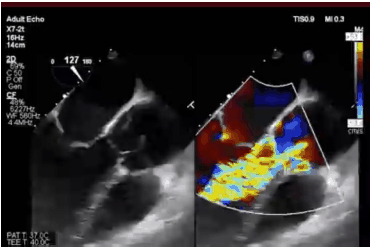

Identifique a etiologia mais provável de regurgitação aórtica baseada na imagem abaixo.